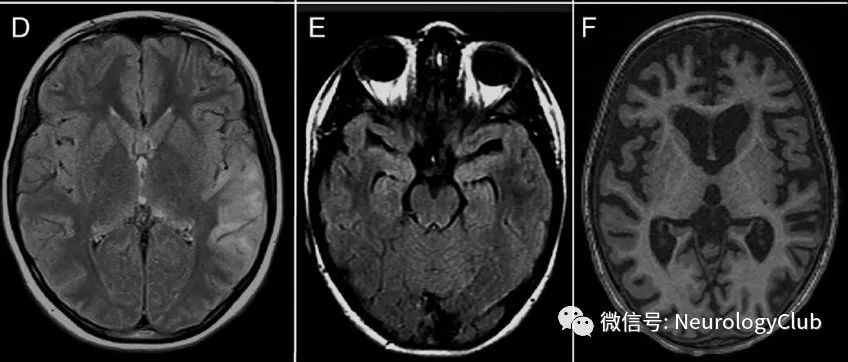

19岁男性,表现为逐渐加重的疲劳、白天过度嗜睡和头痛2月。患者被注意到有意识模糊、定向障碍和幻觉。查体时患者神志清,能够遵嘱完成简单的任务。但无法流利说话或回答问题,并表现出不受约束的行为(disinhibited behavior)。由于患者的脑病表现,行神经影像学检查,结果显示下丘脑、额叶下内侧、扣带回、颞叶内侧和中脑背侧对称性T2WI和液体衰减反转恢复序列(FLAIR)高信号(图1)。(图1:中脑喙侧水平的轴位MRI可见[A]额叶下内侧T2高信号;[B]下丘脑、乳头体[箭]、背侧中脑和导水管周围灰质[*]FLAIR高信号;[C]颞叶内侧[箭头]和额叶下内侧[箭]T1增强后强化;侧脑室水平的轴位MRI可见[D]扣带回T2高信号;[E]胼胝体膝部膝FLAIR高信号[箭];[F]扣带回T1增强后强化[箭])...